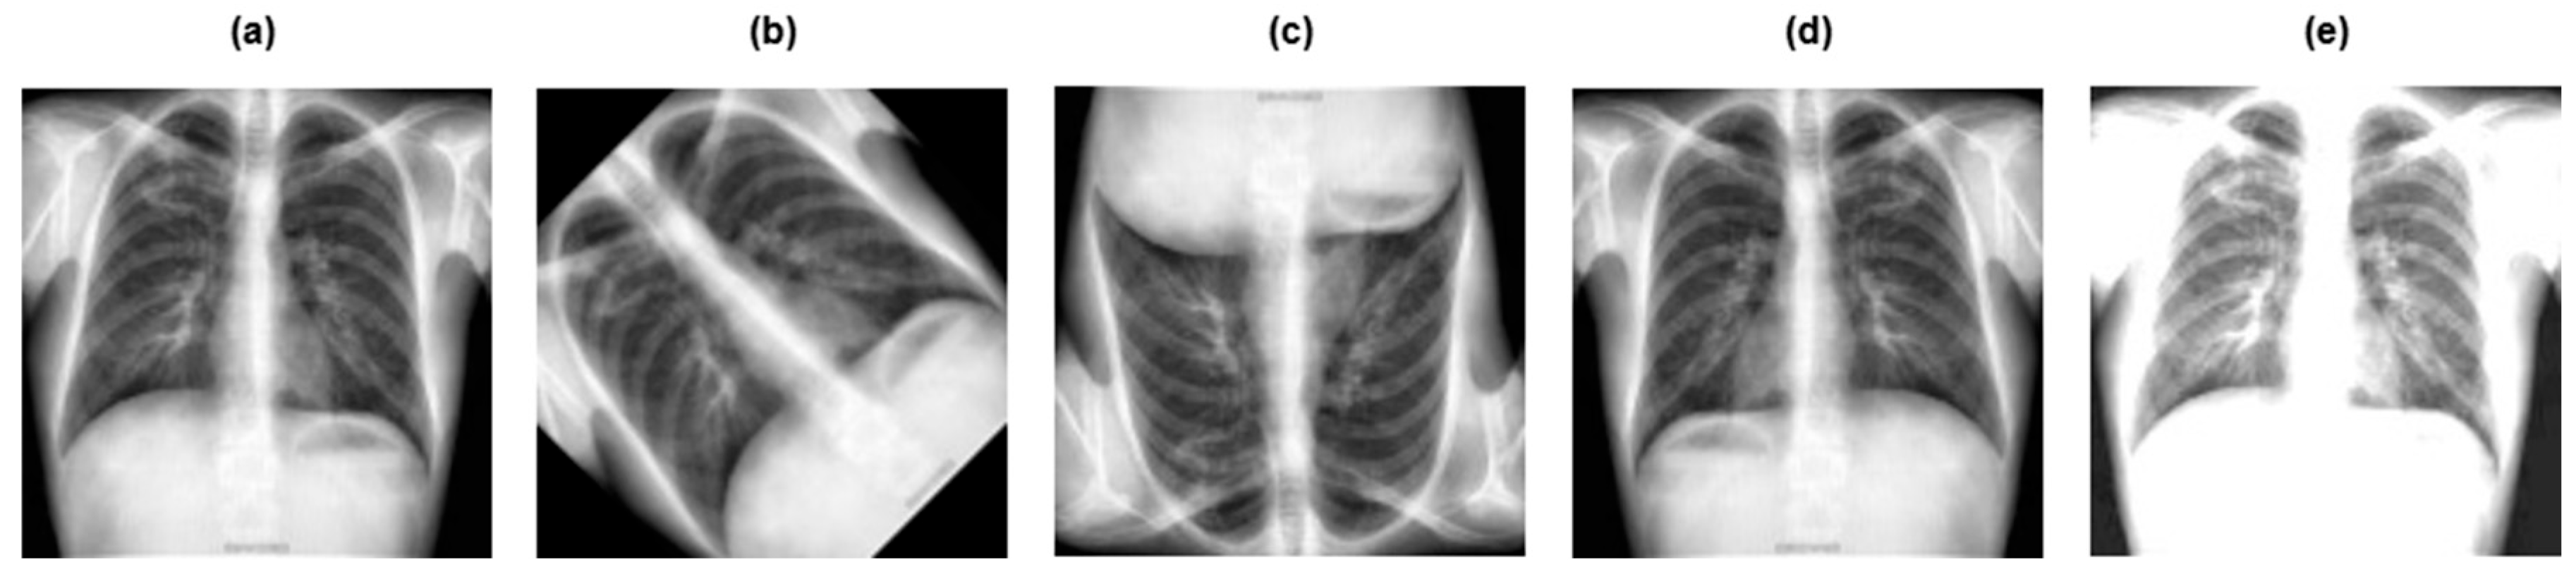

3.2. Data Preprocessing

- •

- Grayscaling: This refers to the conversion of RGB images to grayscale.

- Image resizing: The grayscale image was rescaled to a particular size, that is 128 × 128 pixels.

- Contrast Limited Adaptive Histogram Equalization (CLAHE): This improves the contrast of the image, making the tuberculosis area more pronounced and clearer.

- Image normalization: Normalization adapts the intensity range of individual pixels, typically to make the pixel values of an image more consistent and uniform to the human eye.

3.3. Data Augmentation